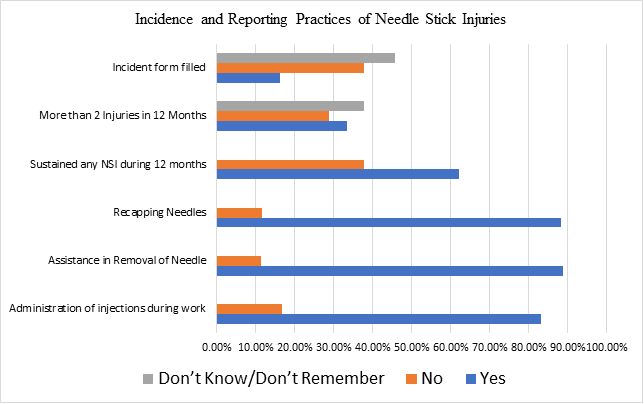

Understanding Needle Stick Injuries and Preventive Practices Among Healthcare Professionals at Tertiary Care Hospital Swat, Pakistan

Background: Healthcare workers (HCWs) are at the highest percentage of getting exposed to percutaneous injuries. Those exposures include blood and...Read More